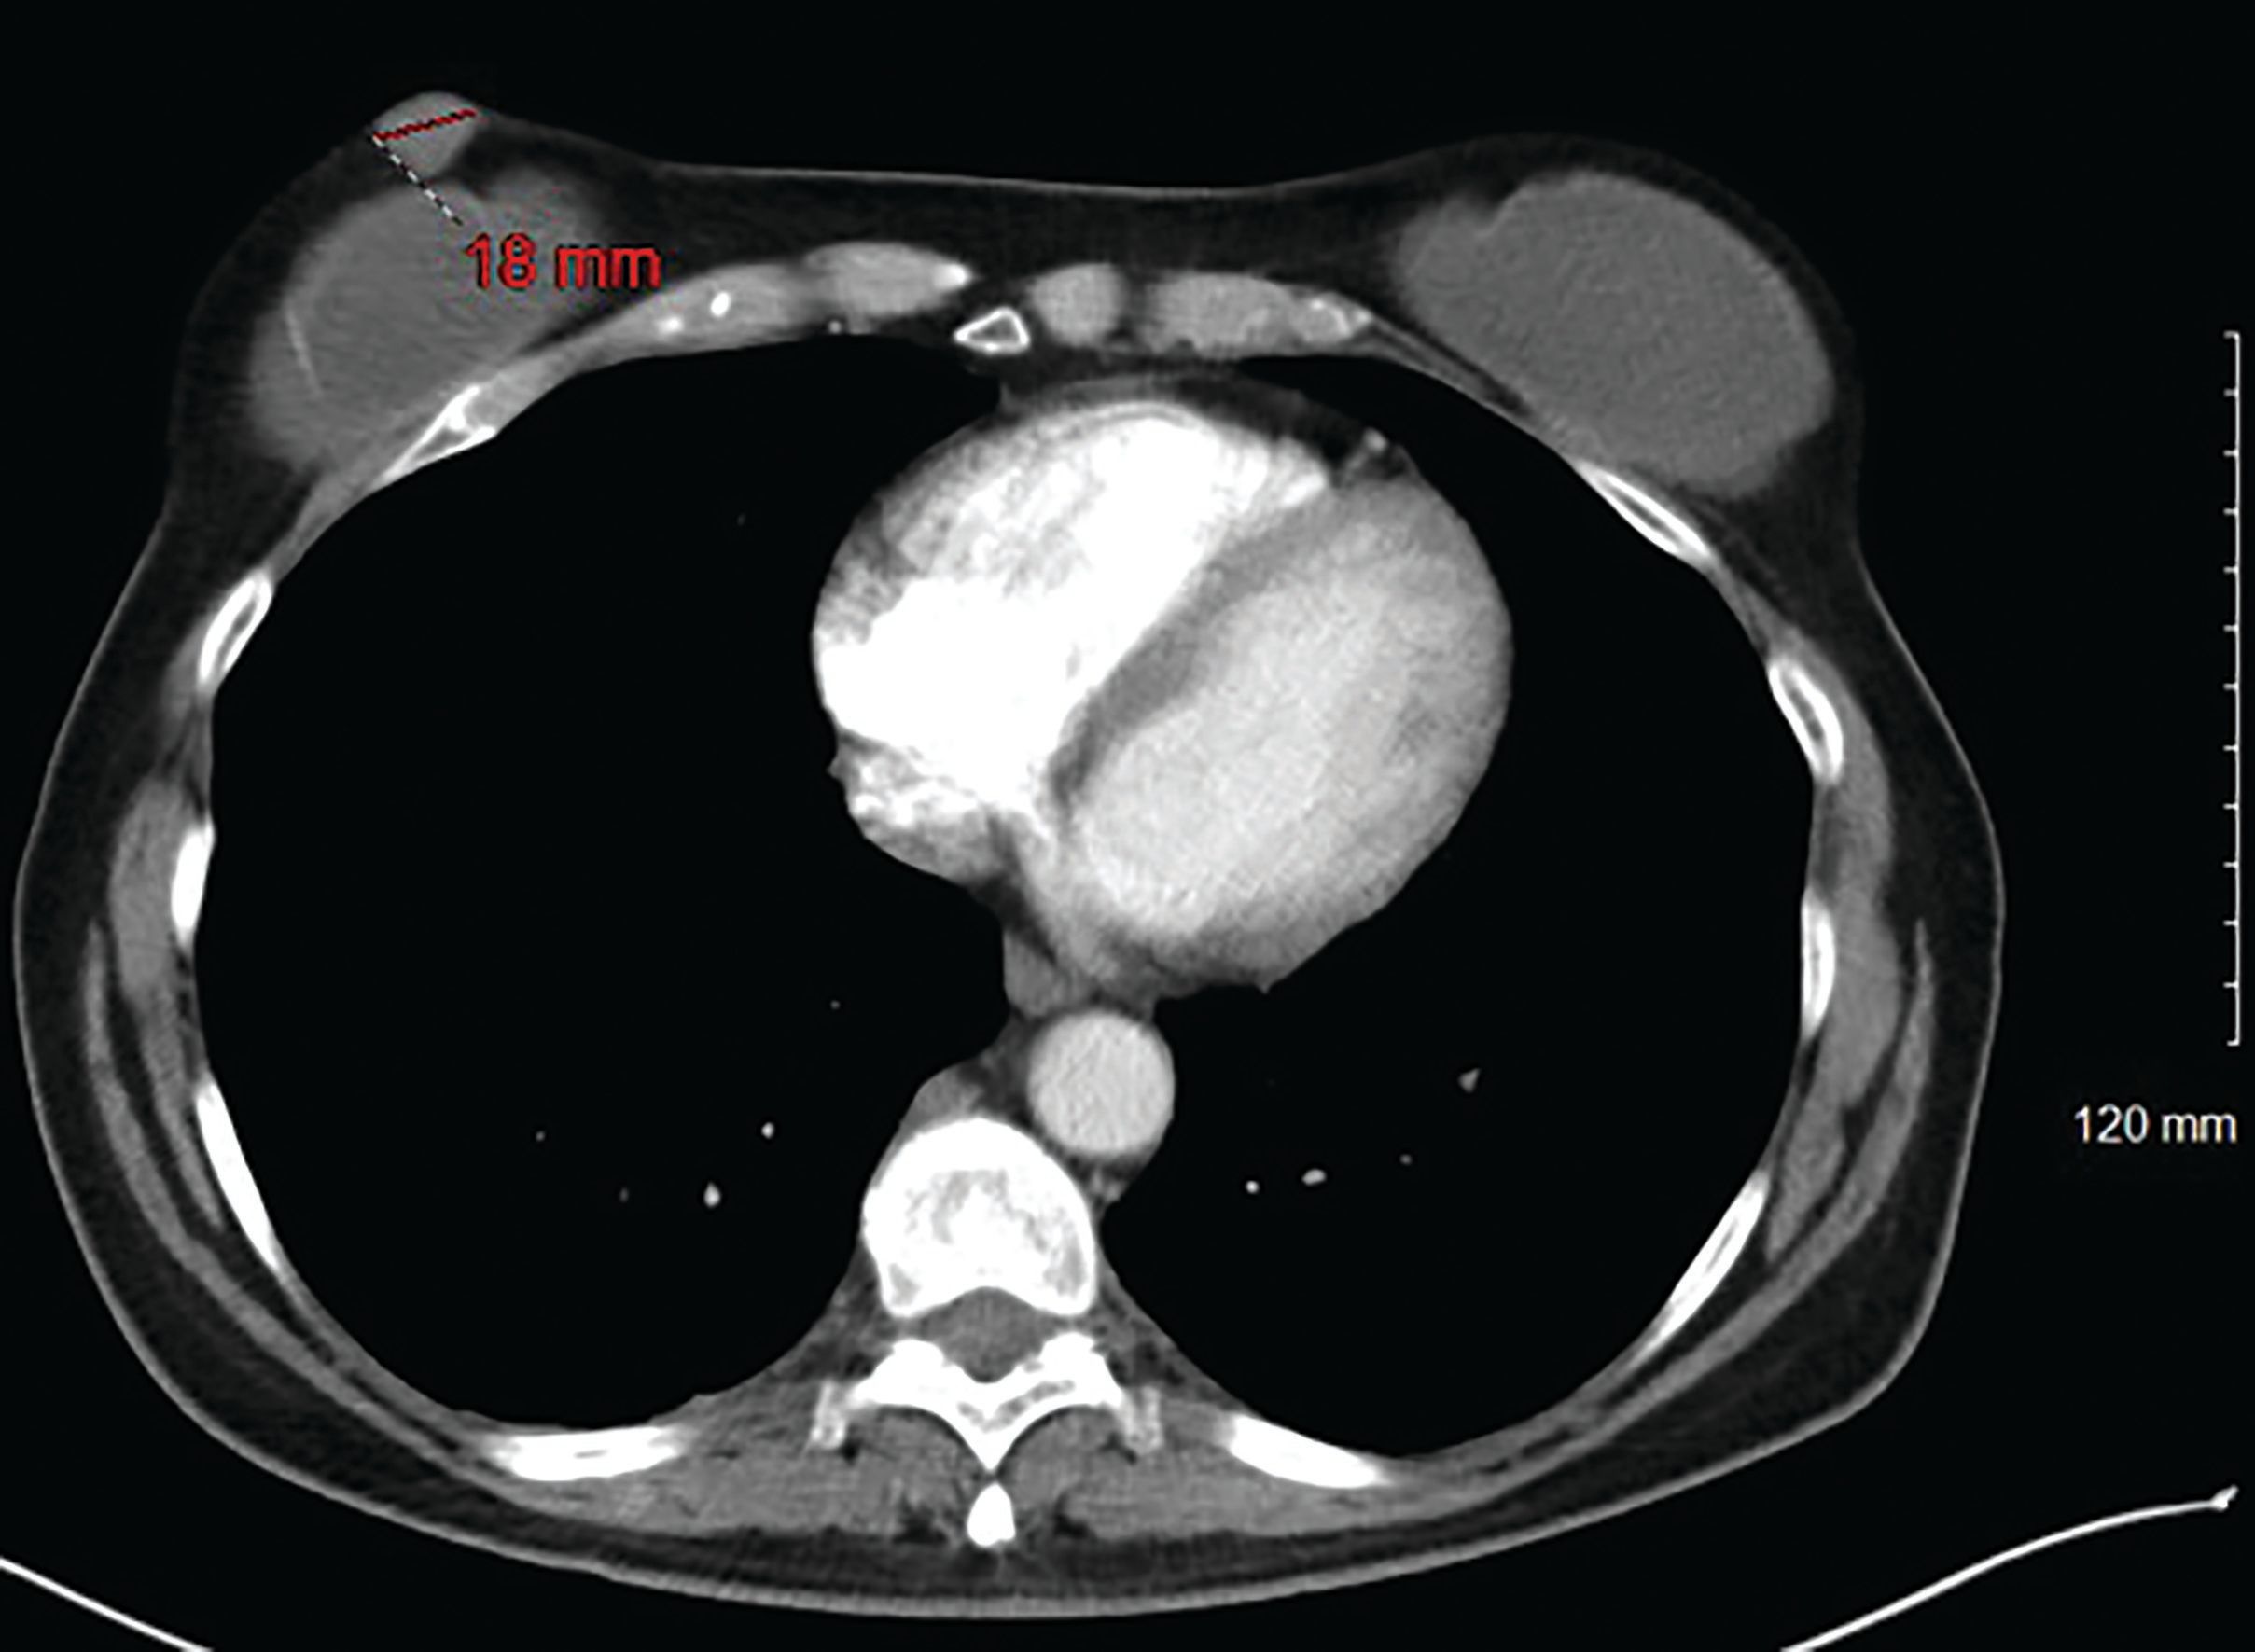

Figure 2. CT Image of breast nodule before chemotherapy

A 57-year-old white woman presented with a subcutaneous, purplish, 1.8-cm nodule in the lower middle of her right breast (Figure 1). Past medical history was significant for bilateral silicone breast implants 10 years ago, and a diagnosis of limited-stage small cell lung cancer treated with etoposide/cisplatin plus concurrent chest wall radiation which led to complete remission 1 year ago. In evaluation of this skin nodule, a computed tomography (CT) scan of the chest and an ultrasound-guided biopsy of the breast nodule was performed. The CT scan of the chest confirmed the presence of bilateral breast implants with a 1.8-cm breast nodule in the middle lower quadrant of the right breast, and a right axillary lymph node (Figure 2). Pathology of tissue from the breast nodule biopsy are shown in Figure 3 and Figure 4.